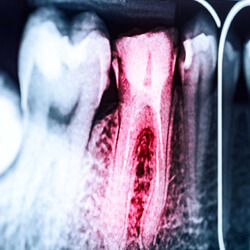

The Root Canal Process

Root canal therapy is used in order to save teeth that are damaged and ultimately eliminate discomfort. First, you are administered a local anesthetic to ensure that you’re comfortable during the procedure. The area will be completely numb, so you won’t be able to feel a thing.

Once the area is completely numb, your dentist will make a small hole in your enamel and remove all of the damaged and infected tissue from the inside of your tooth. Afterwards, they will clean and sanitize the tooth to ensure that it is completely free from bacteria. Lastly, the tooth is filled with a biocompatible filling material. In many cases, a dental crown is placed overtop the tooth to keep it safe from further damage.